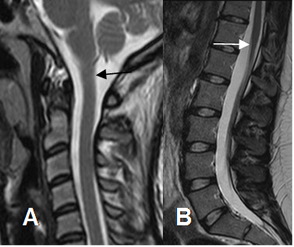

La medula espinal es la continuación del bulbo raquídeo. Está rodeado por las meninges y se extiende hasta L1-L2. (Fig 6).

Fig 6. Medula espinal.

A: RM sagital en T2. Unión craneoespinal, como continuación del bulbo.

B: RM sagital en T2.Ubicación del cono medular sobre la unión dorsolumbar.